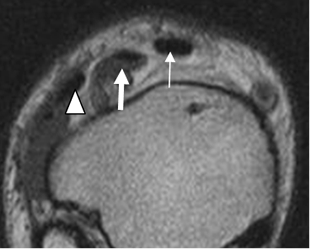

Fig 19. Fascia plantar normal.

A y B: RM axial en T1 y C: RM coronal en T1. Rama medial (Flecha delgada), central (Flecha gruesa) y lateral (Cabeza flecha).

Fig 20. Fascia plantar normal.

A: RM sagital en T2 y B: RM sagital en STIR. Estructura hipointensa en todas las secuencias.